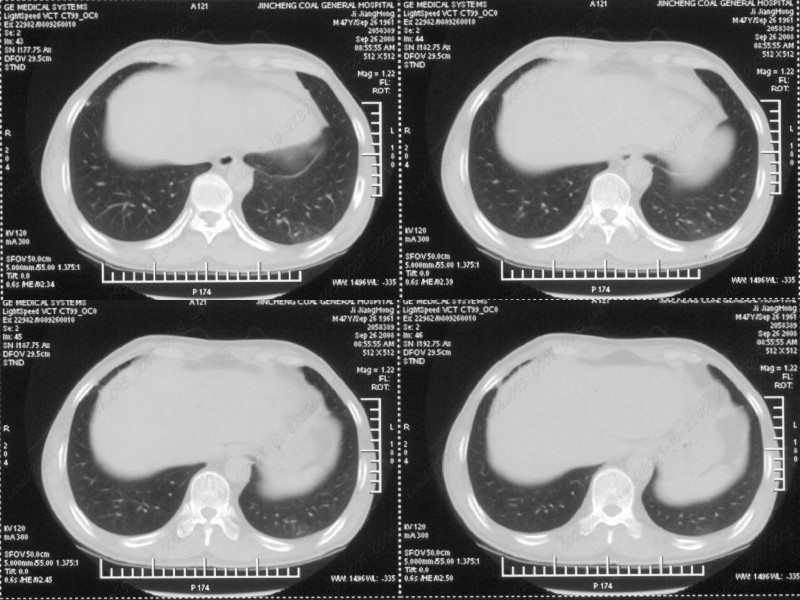

男性,47岁。胸部不适一年,ct检查发现右胸膜下结节。http://www.radida.com/bbs/forum.php?mod=viewthread&tid=46094

病灶周围似有纤维化征像,增强明显强化,但中央可见点状低强化区,考虑慢性病变可能如炎性假瘤等,病灶边缘部分毛糙有切迹,双侧胸腔少量积液影,不除外恶性

汇报临床诊断:右肺动脉分枝栓塞

考虑心脏疾患引起的右侧斜裂增厚。

右肺静脉充盈缺损,左心房体积小,右肺动脉远端动脉充盈缺损,右肺血管影细小,考虑;右肺动脉远端栓塞.

右肺中叶外侧段占位,考虑周围型肺癌伴局限性肺气肿,不除外炎性假瘤